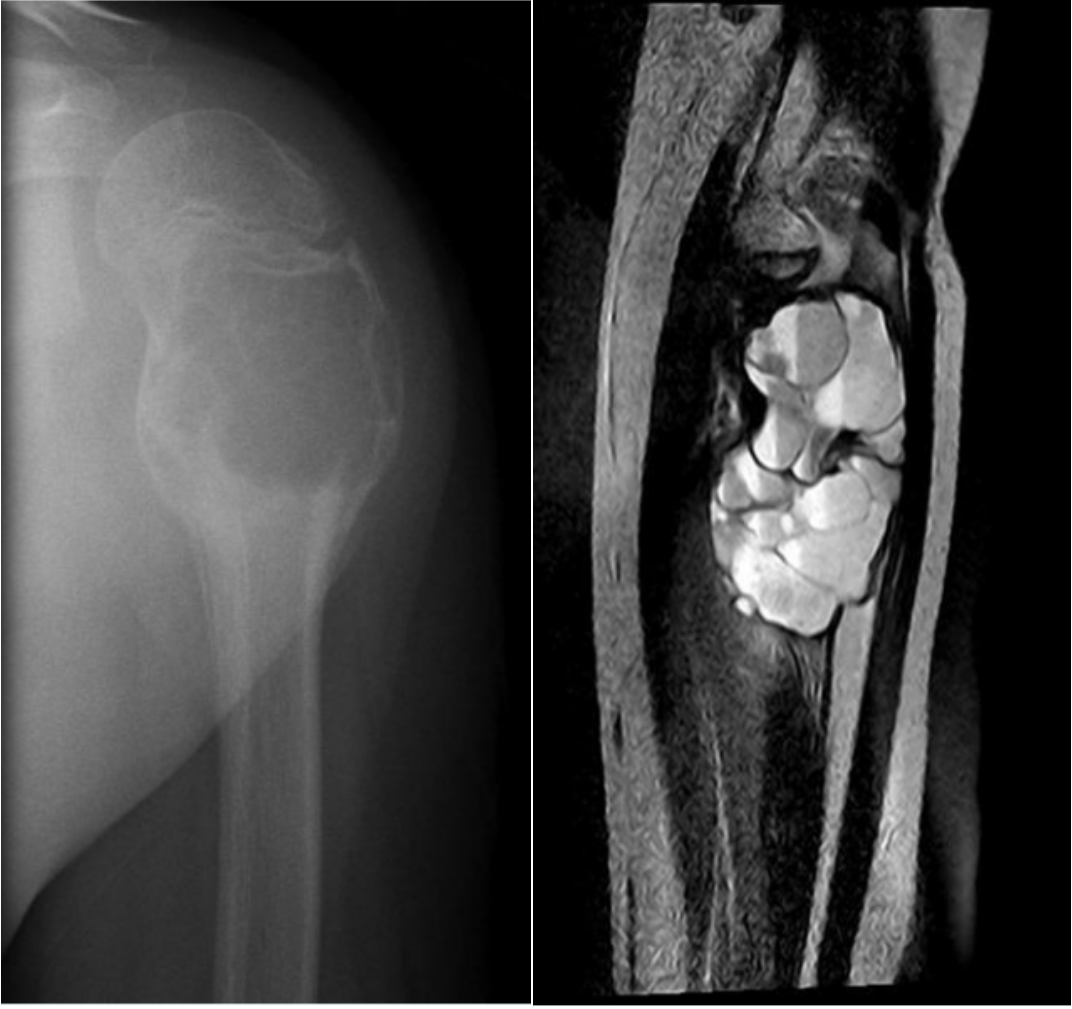

我们先来看下面两张片子。

不难看出,在骨头里有一格一格类似泡沫一样膨大且透亮的结构,图2更是看上去像水泡一样长在骨头里。出现这种情况的原因呢,是因为长了骨肿瘤,这种肿瘤我们称之为动脉瘤样骨囊肿。

动脉瘤样骨囊肿,aneurysmal bonecyst ,有个非常好记的英文简写,叫ABC。动脉瘤样骨囊肿是一种好发于儿童和青少年的良性单发骨肿瘤,它的特点是在肿瘤内能看到如上图的均匀泡沫状透亮区。动脉瘤样骨囊肿是由大小不等充满血液腔隙组成的膨胀性溶骨性病变,囊壁为含骨样组织、骨小梁和破骨细胞型巨细胞的结缔组织。患者的症状是局部疼痛肿胀,功能障碍,如果病灶位于脊椎时,可以产生脊髓压迫症状。